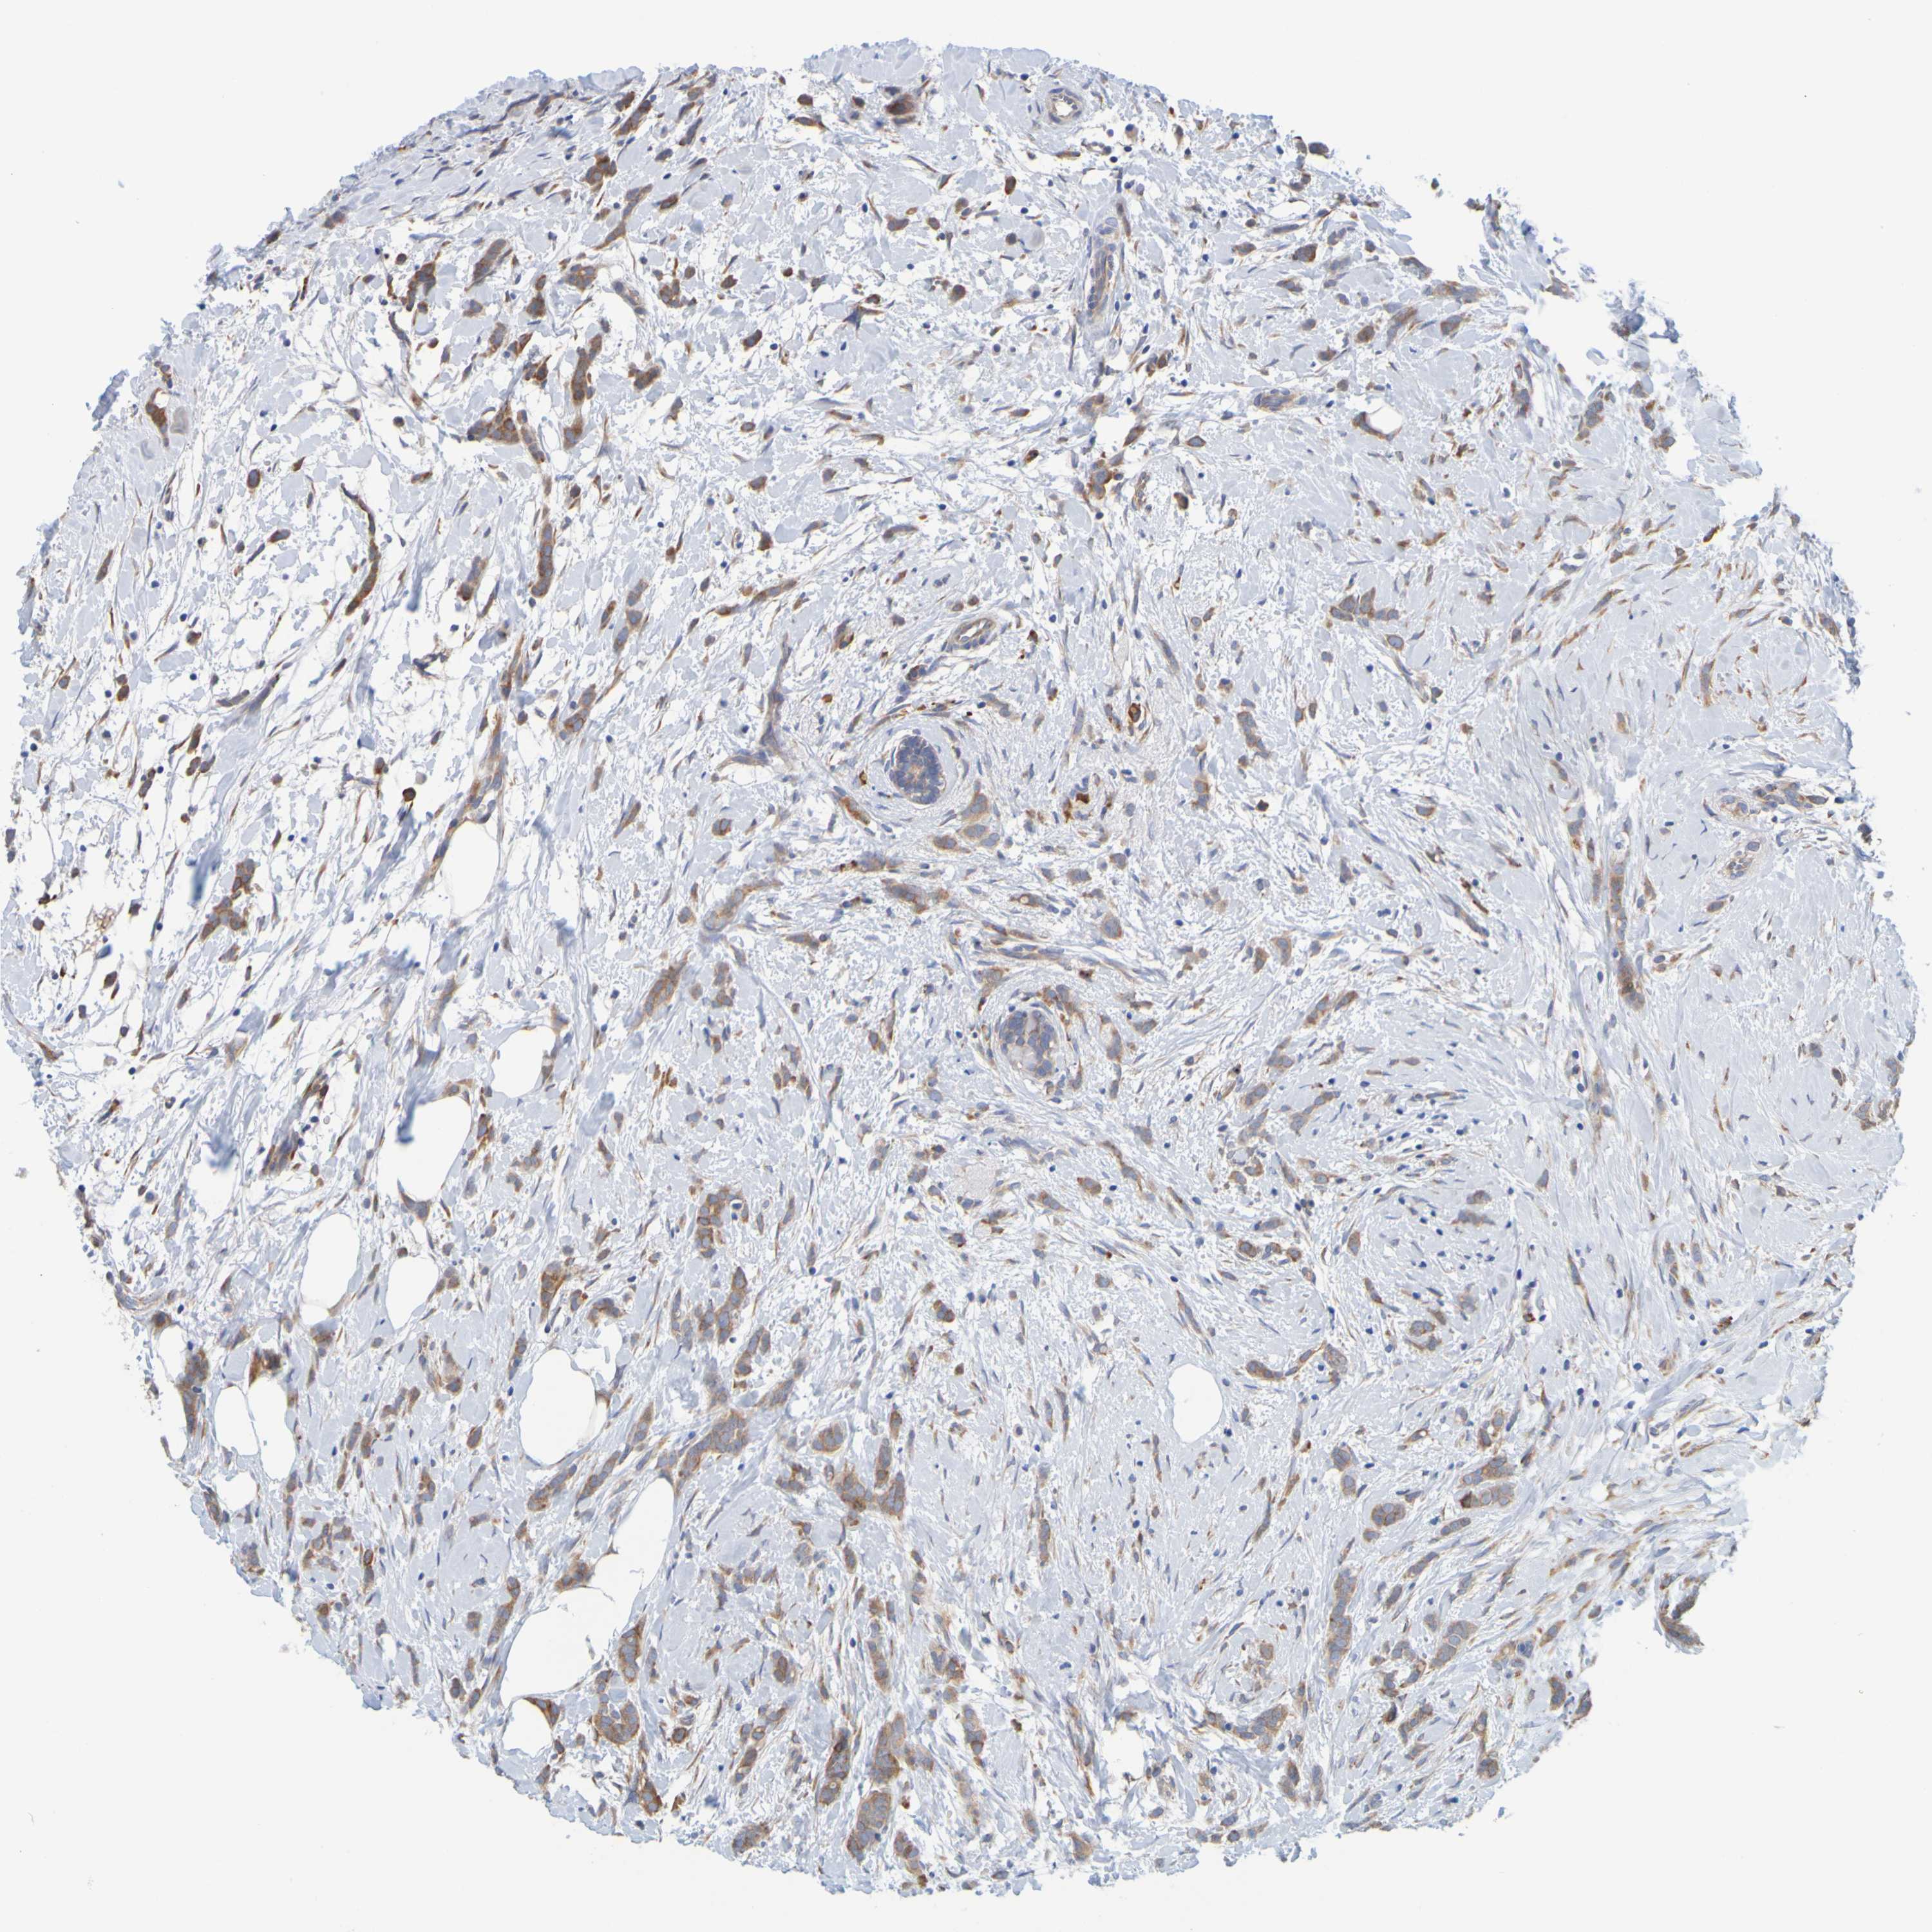

CANCER BREAST CANCER Show tissue menu

BRCA TCGA BRCA VALIDATION PROTEIN EXPRESSION